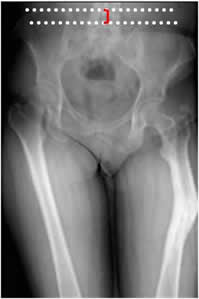

El desbalance pélvico se determina mediante la distancia entre líneas horizontales, que pasan sobre el borde superior de las crestas iliacas. (3). (Fig 106).

Fig 106. Acortamiento.

Rx AP. Acortamiento del fémur izquierdo, como secuela de fractura consolidada en varo. Se encuentra desbalance pélvico, con elevación de la cresta iliaca derecha.